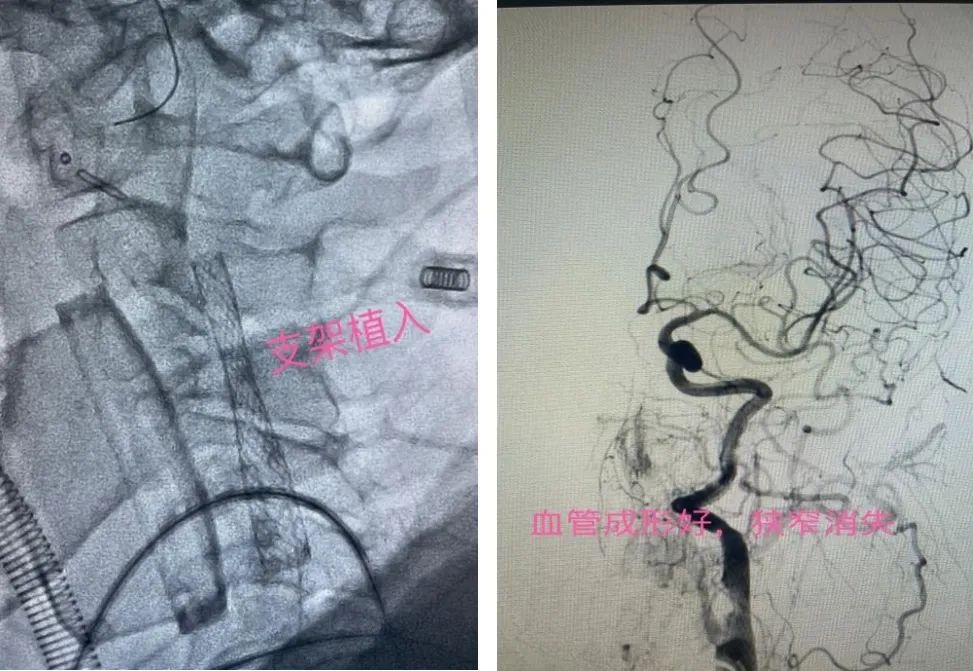

【医讯速览·新闻】第66期:我院神经外科成功开展首例“大脑中动脉取栓术+颈动脉支架植入术”